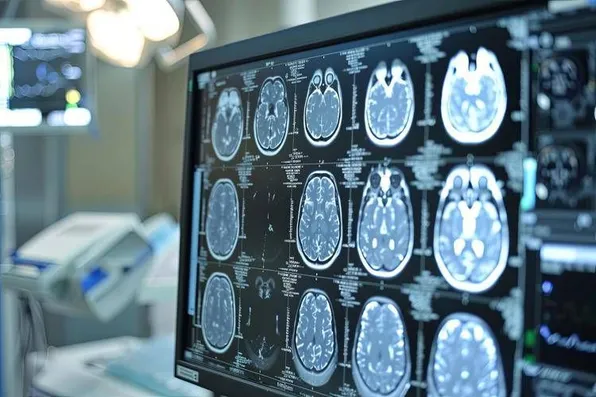

In occasione della Giornata Mondiale dell'Alzheimer, che si celebra domenica, 21 settembre, la Società italiana di neurologia (Sin) richiama l’attenzione sulla necessità di un cambiamento concreto nei percorsi di cura e di assistenza, affinché la malattia diventi una reale priorità sanitaria e sociale, non solo in Italia ma a livello globale. Negli ultimi anni - riporta una nota - la ricerca scientifica ha aperto nuovi scenari, grazie all’introduzione di farmaci innovativi e allo sviluppo di biomarcatori sempre più affidabili per una diagnosi precoce. Tuttavia, questi progressi rischiano di rimanere 'parziali' se non accompagnati da un’evoluzione parallela del sistema di presa in carico dei pazienti. Per la Sin è urgente rafforzare l’organizzazione dei servizi, garantendo una risposta più efficace, continua e sostenibile ai bisogni delle persone con demenza e delle loro famiglie.

La possibilità di intervenire in modo più tempestivo, resa oggi concreta dai nuovi strumenti diagnostici e terapeutici, impone un cambio di paradigma. La demenza non può più essere considerata soltanto una condizione da accompagnare nelle sue fasi terminali, ma deve essere affrontata come una malattia cronica, che richiede attenzione sin dalle sue prime manifestazioni, con l’obiettivo di rallentarne l’evoluzione e attenuarne l’impatto sulla quotidianità. In questa prospettiva, la Sin sottolinea l’importanza di sviluppare modelli assistenziali integrati, capaci di accompagnare le persone lungo tutto il percorso della malattia, in modo uniforme su tutto il territorio nazionale. Dalla prevenzione alla diagnosi, dal trattamento farmacologico al sostegno per familiari e caregiver, ogni fase deve essere parte di un sistema unitario, accessibile e orientato alla persona. La Giornata mondiale dell’Alzheimer rappresenta quindi un’occasione per rimettere al centro dell’agenda pubblica una delle sfide più complesse del nostro tempo. La Sin rinnova il proprio impegno a collaborare con istituzioni, professionisti e società civile, per costruire insieme un modello di assistenza più preparato, più umano e capace di evolvere con la scienza.